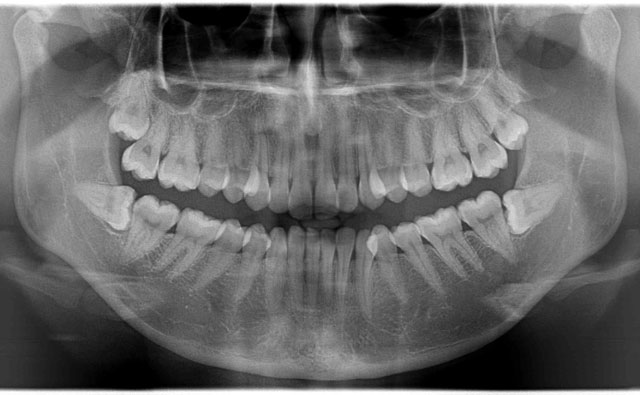

4.パノラマX-ray

パノラマサイズのレントゲンで、全部の歯を撮影することができます。

主に、親知らずの位置や、歯周病の進行状態を知る為、子供の歯の生え換わりの時期には永久歯の状態を知る為に撮ります。